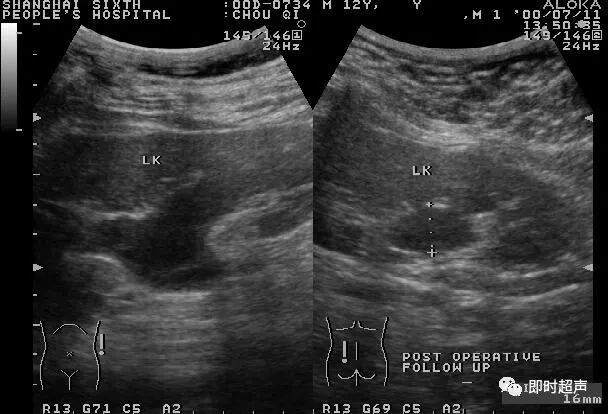

图4-1-5 肾积水声像图 左图为菱角型

轻度肾积水,在声像图上出现肾窦分离,肾盂肾盏均有轻度积水,但肾实质厚度和彩色血流不受影响。中度肾积水,肾窦回声中出现无回声区,因各人肾盂肾盏原来形态不同,显示各种形态的肾积水声像图,肾盏积水明显可见(图4-1-3~图4-1-5)。重度肾积水,肾盂肾盏明显扩大,显示各形无回声区,肾实质明显变薄,肾实质内彩色血流明显减少或消失。